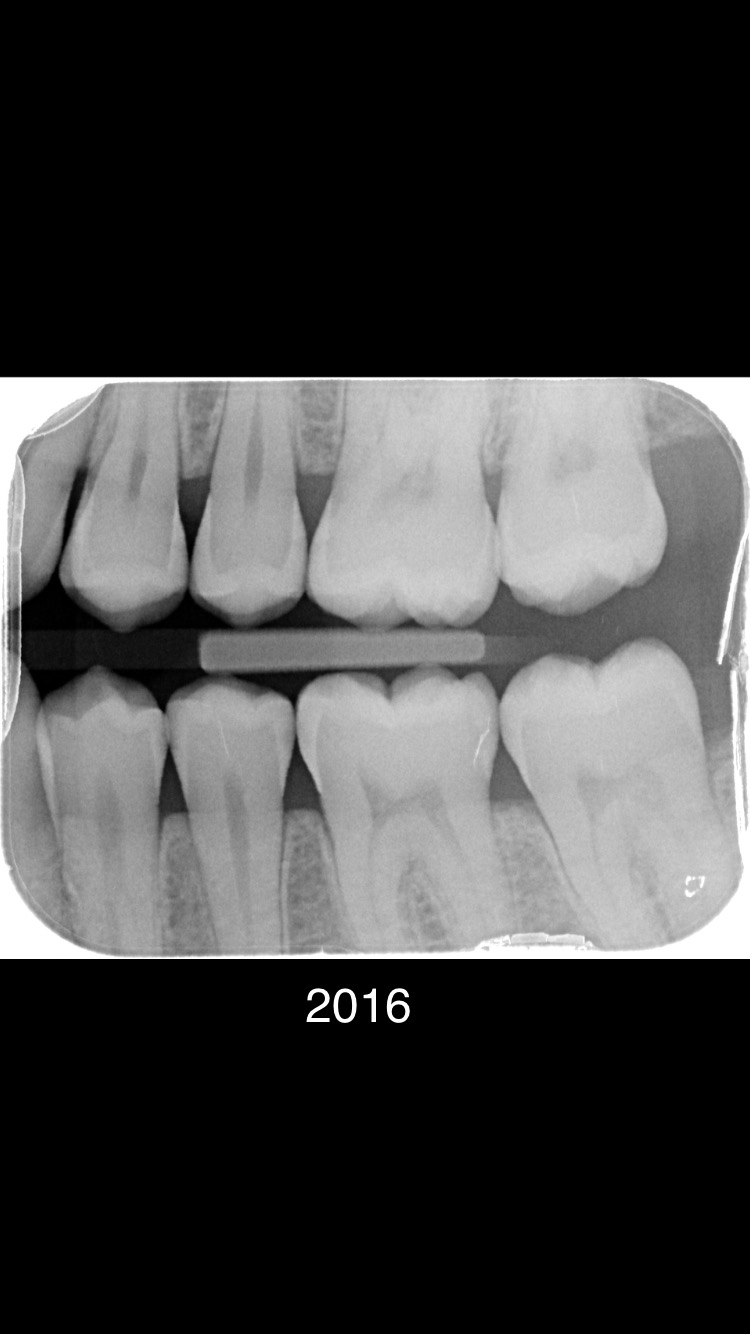

Er zijn meerdere beginnende plekjes maar die zijn nog niet door het glazuur dus hoeven nog niet aangepakt te worden. De vier in de linker boven en onderkaak gevonden "gaatjes" zou ik ook aanpakken. 25.26.35,36.......24 kan ik niet goed beoordelen dus twijfel.16 zou ik nog niet doen. In 2021 waren er links enige die net wel of net niet door het glazuur zijn.. dus ik kan begrijpen dat uw tandarts dat in de gaten heeft gehouden, gemonitord. Maar wat heeft u gedaan tussen 2020/2021 en 2023.. Gebruikt u wel ragers elke dag???>of andere reiniging hulpmiddelen voor tussen de tanden en kiezen. Let op uw voeding/drank gebruik... beperk het aantal invloed momenten op uw gebit tot 6. etc etc. dit gaat fout. Op de status praesens v uw gebit zie ik maar 5 aantekeningen niet 7. Maar ik ben niet goed in rekenen.

Helaas alle praktijken moeten verdienen... Het is een onderneming geen charitatieve instelling. Alle prijzen worden voor ons door NZA bepaald hebben wij niets over te zeggen. Lees mijn advies hierboven wat gaatjes betreft. Niet elke dag tussen alle tanden en kiezen een rager gebruiken vind ik zeer onverstandig. Zie alle defecten...zijn allemaal tussen de kiezen waar een tandenborstel niet maar een rager wel kan komen. Wanneer bent u voor het laatst bij de tandarts geweest??. Blijkbaar gaat er iets fout. Houdt bij zoals ik heb aangegeven en bespreek dat met de mondhygiënist. Laat ook daadwerkelijk zien hoe u reinigt er gaat iets fout. Dat v niet elke dag een rager gebruiken is er een. Als al beginnende "gaatjes" zijn niet elke 6 mnd naar de tandarts gaan is nr 2. Foto v 2021 was niet alarmerend maar toen is iets fout gegaan. Dus in twee jaar tijd.

Bedankt voor uw bericht. Ik zal de gaatjes vullen. Maar de nieuwe tandarts heeft nog niet de oude foto’s gezien. Kan dit effect hebben op het oordeel van hem om 5 gaatjes te vullen? Ik had het idee dat alleen 36 een gaatje had. Bij de rest voel ik niks. Ik zie wel donkbruine aanslag tussen de hoeken van waar de ragers z’n werk deden. Ik had de oude tandarts in 2021 hierover gesproken. Hij zei dat het komt in verband met teruggetrokken tandvlees. Is het verstandig om na elke maaltijd te flossen en ragers te gebruiken?

Je gaat toch niet zelf de gaatjes vullen ??.Heeft u mijn verbaasde vraag hierboven gelezen of u een rager gebruikt. Ik ben blij als mijn cliënten 2xdgs een rager gebruiken, minimaal 1xpd.n Het gaat om de meest recente foto. De oude foto's geven een beeld v progressie v defecten.